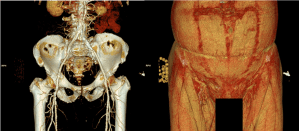

torso CTA